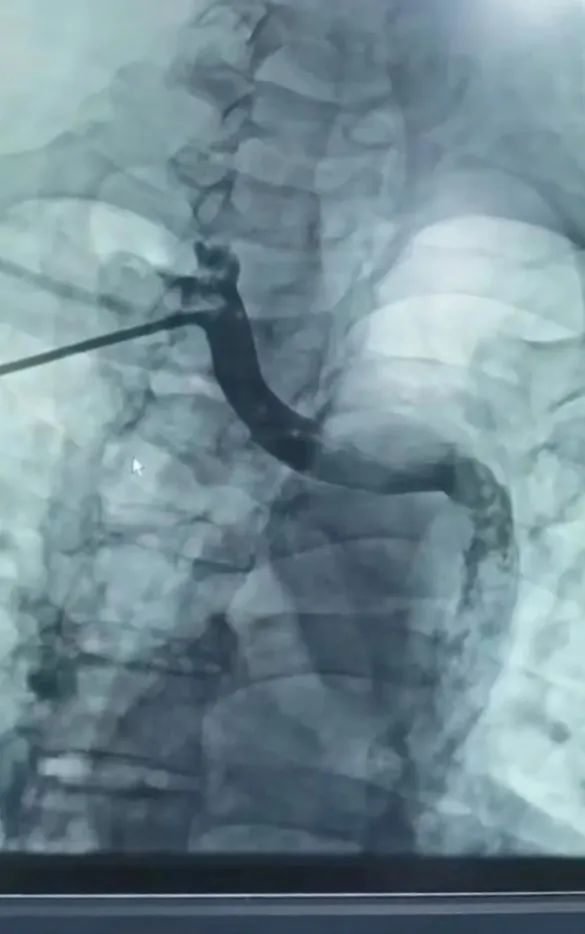

先天性永存左上腔靜脈(DSA)

Micra無導(dǎo)線起搏器植入術(shù)后(DSA)